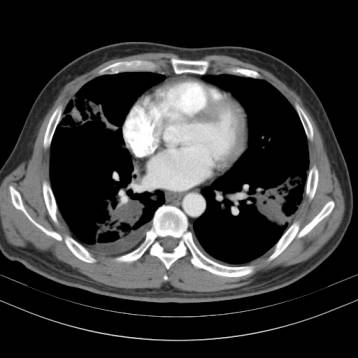

少增强

肺结核因为干酪性坏死,增强CT强化一般不明显!但是,有些肺结核在增殖阶段,生长活跃,没有形成明显坏死,有可能显著增强。这个要综合考虑。但是大多数肺结核增强一般不会显著强化。肺癌生长需要血供,常常显著强化。

简单的说,就是增强CT上,病灶越白,强化也明显,肿瘤、一般细菌感染引起炎性结节常常明显强化,肺结核强化不明显。

上图是肺结核增强CT,病灶几乎无强化,和下面差别很大。